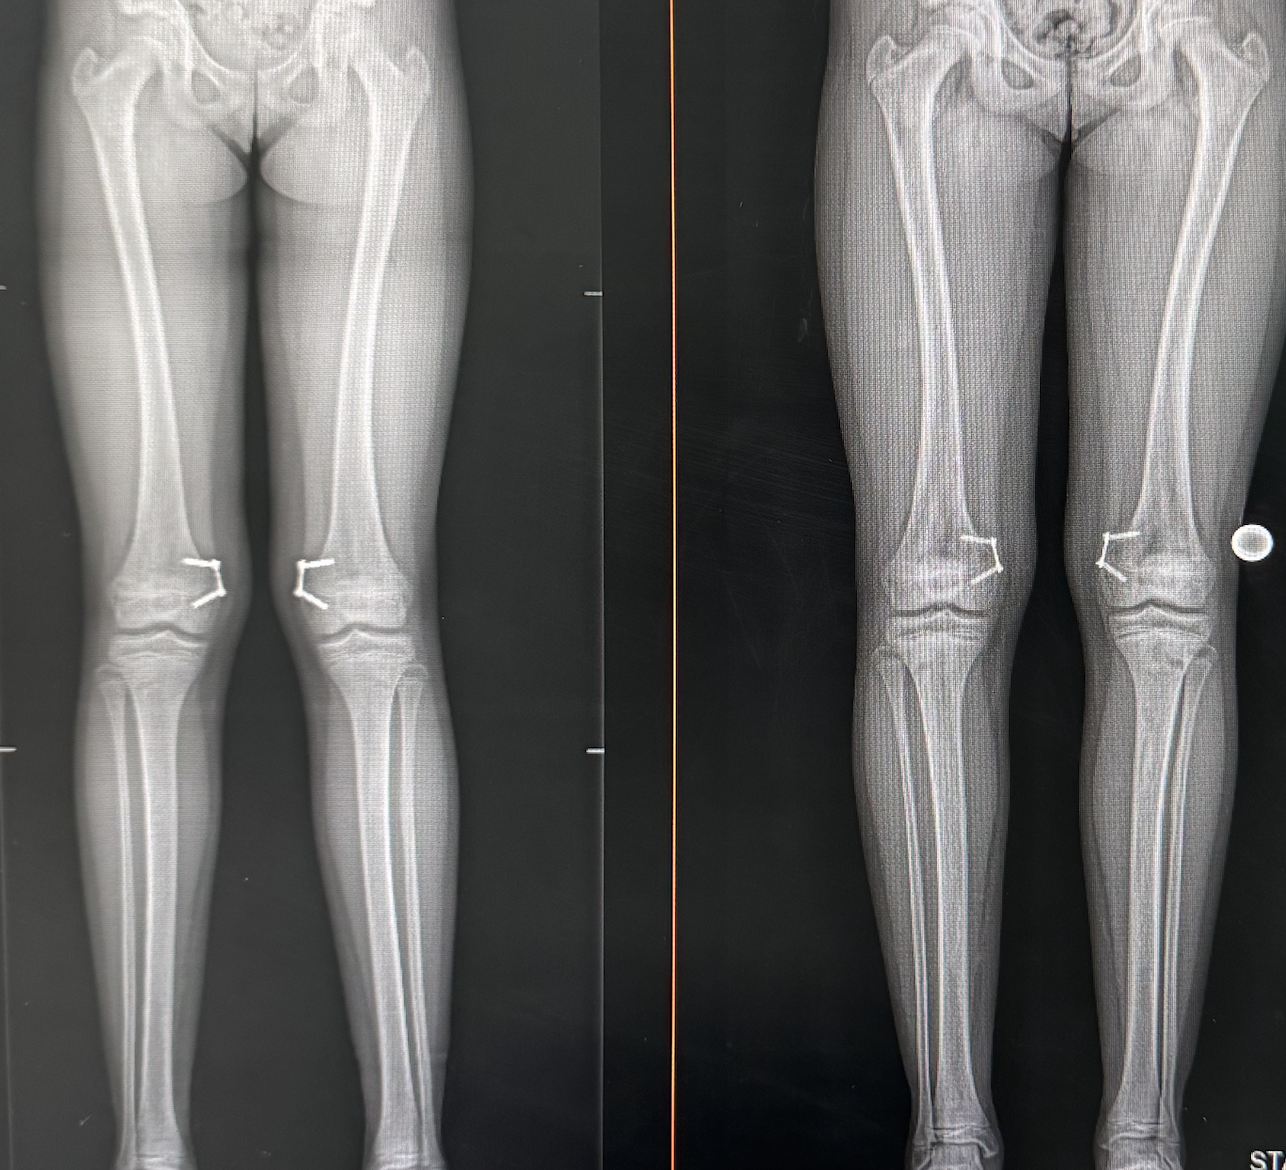

Genu valgum knock knees

Femoral 8 plates for genu valgum

X-rays before, and after 11-year-old girl treated with Hemi epiphysiodesis using plates on the thighbone, distal femur.